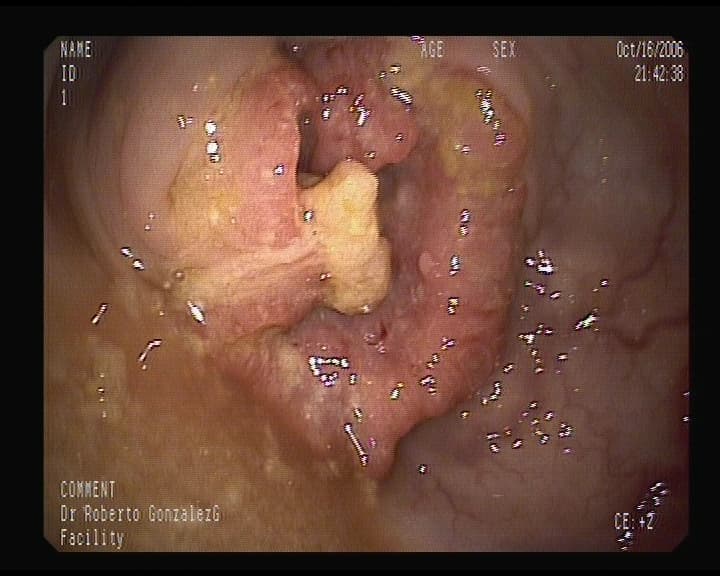

Cicatriz de Úlcera grande en estómago

Tras tratamiento médico la úlcera cicatrizó, Biopsias negativas. No obstante se debe reexaminar y nueva toma de biopsias en 3-4 meses. Sospechosa por su tamaño.